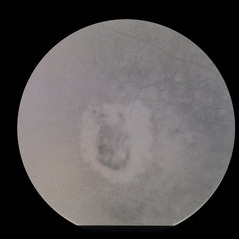

ARMD, SRNVM ARMD, SRNVMAug 7 2013 by H. Michael Lambert, MD ARMD, SRNVM, 79-year-old white female, 20/300. Condition/keywords: subretinal neovascularization (SRNV)